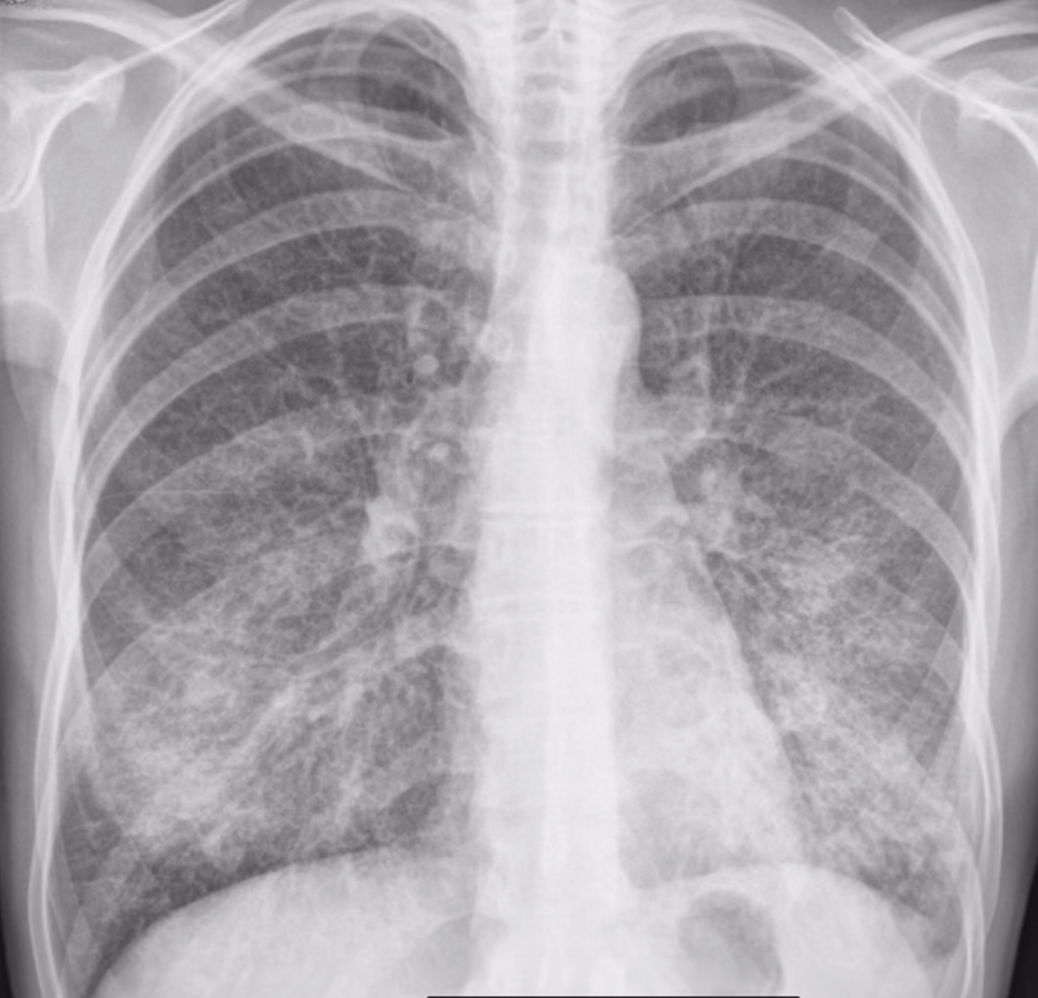

15

Q

M20a llega porque tiene fatiga hace una semana. Siente escalofríos y tiene tos seca.

TA: 120/70, FC: 92, FR: 22, T: 37.8°C, SatO2: 90%

Exploración: Estertores en ambas bases pulmonares. ¿Microorganismo responsable?

16

Descripción

A

Patrón reticular fino en ambos pulmones.